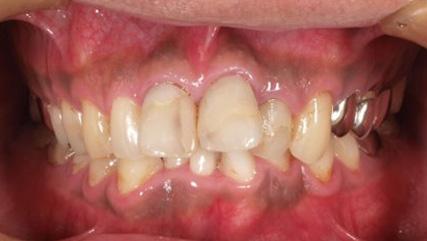

治療前

治療終了前

でこぼこがある状態になります。乱ぐい歯とも言われます。見た目がよくない審美障害が主な問題点ですが、その他にもでこぼこが多いことで、歯ブラシによる清掃性が悪くなり、結果、虫歯や歯周病のリスクも上がってしまいます。治療期間が短く済むことも多い為、気になった段階で早期に相談された方が良いと思います。